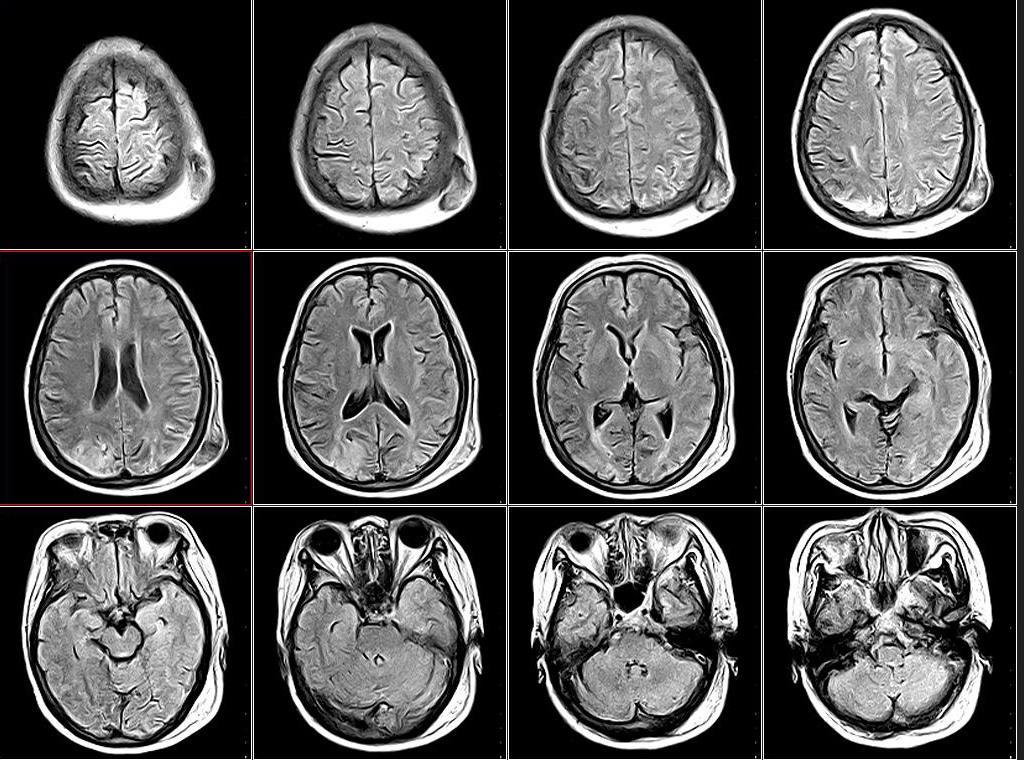

2、颅脑MRI检查

可发现脑干和小脑萎缩。MJD患者的脑桥横向纤维在T2加权图像上 呈高信号 ,偶发性橄榄桥萎缩者为高信号,对照组为 低信号 。